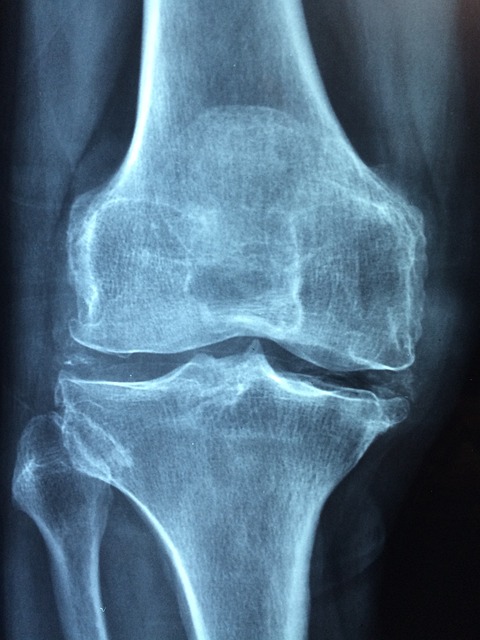

골다공증은 뼈 밀도가 낮아지고 약해져 쉽게 부러지는 상태를 말합니다. 이는 나이가 들면서 자연스럽게 발생할 수 있지만, 특히 폐경 후 여성들에게 흔히 나타나는 질환입니다.

주요 원인으로는 나이 증가, 호르몬 변화, 영양 부족, 운동 부족 등이 있습니다. 골다공증은 뼈의 강도가 약해져 골절 위험을 크게 증가시키며, 초기에는 뚜렷한 증상이 없지만 시간이 지나면서 키가 줄어들거나 허리 통증이 발생하고, 작은 충격에도 쉽게 뼈가 부러질 수 있습니다.